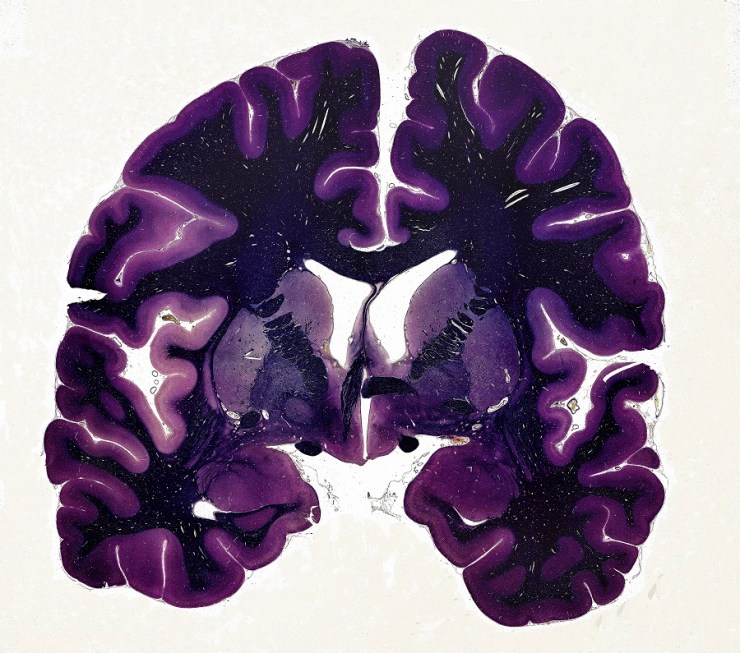

The large, folded outer part of the human brain is called the cortex, and is responsible for decision-making, language, face recognition, and a lot of the other things that I like to think are what make us human. The word cortex comes from the Greek for husk or outer shell, which underestimates the importance of what the cortex does.

I am studying one particular neurodevelopmental disorder caused by lack of oxygen at birth. It is known to medical specialists as neonatal hypoxia ischaemia. The image on the right shows a cross-section MRI scan of a normal newborn human brain, alongside some babies who have been damaged by oxygen deprivation. You can see that the brains are smaller, the cortex is less folded and it takes up less space inside the skull.